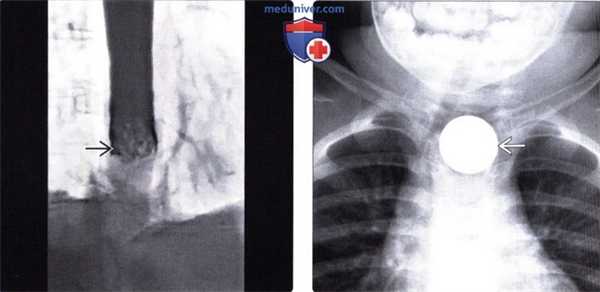

(Слева) При рентгенографии пищевода со взвесью сульфата бария определяется полная обструкция просвета и дефект наполнения - изменения, обусловленные проглатыванием недостаточно разжеванного куска мяса. После его извлечения у пациента было обнаружено кольцо Шацкого.

(Справа) При рентгенографии, выполненной ребенку в возрасте одного года, проглотившему батарейку от часов, в проекции шейного сегмента пищевода визуализируется большая округлая тень. Обратите внимание, что тень (в отличие от моменты с зазубренными краями) имеет ровные очертания. Поскольку батарейка обусловливала стойкое сужение просвета пищевода, потребовалось ее извлечение.